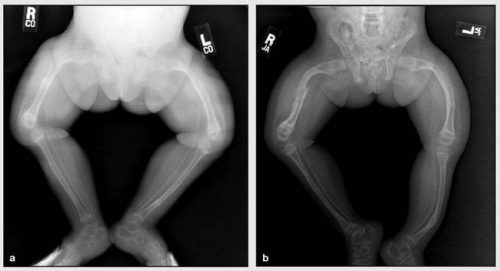

Наиболее распространенными являются травмы длинных костей — берцовой, бедренной, плечевой. Они могут возникать еще в период внутриутробного развития, в процессе прохождения по родовым путям или в первые месяцы жизни. При рождении часто происходят переломы ключиц, конечностей. Особенно часто это случается при использовании вспомогательных акушерских устройств, например, щипцов. При неправильном сращении кость деформируется, наблюдаются патологические изменения в грудной клетке и позвоночнике, которые можно увидеть на фото. Кости черепа размягчаются.

- При 2 наблюдаются выраженные нарушения в формировании скелета: деформация и укорочение костей, образование остеофитов. Ребенок сильно отстает в развитии.

Ренгенологические признаки зависят от степени тяжести патологического процесса. Отмечаются истончение верхнего слоя длинных костей, уменьшение объема тканей, патологические переломы с формированием костных мозолей. Кости черепа у ребенка размягчены, швы между ним зарастают длительное время.